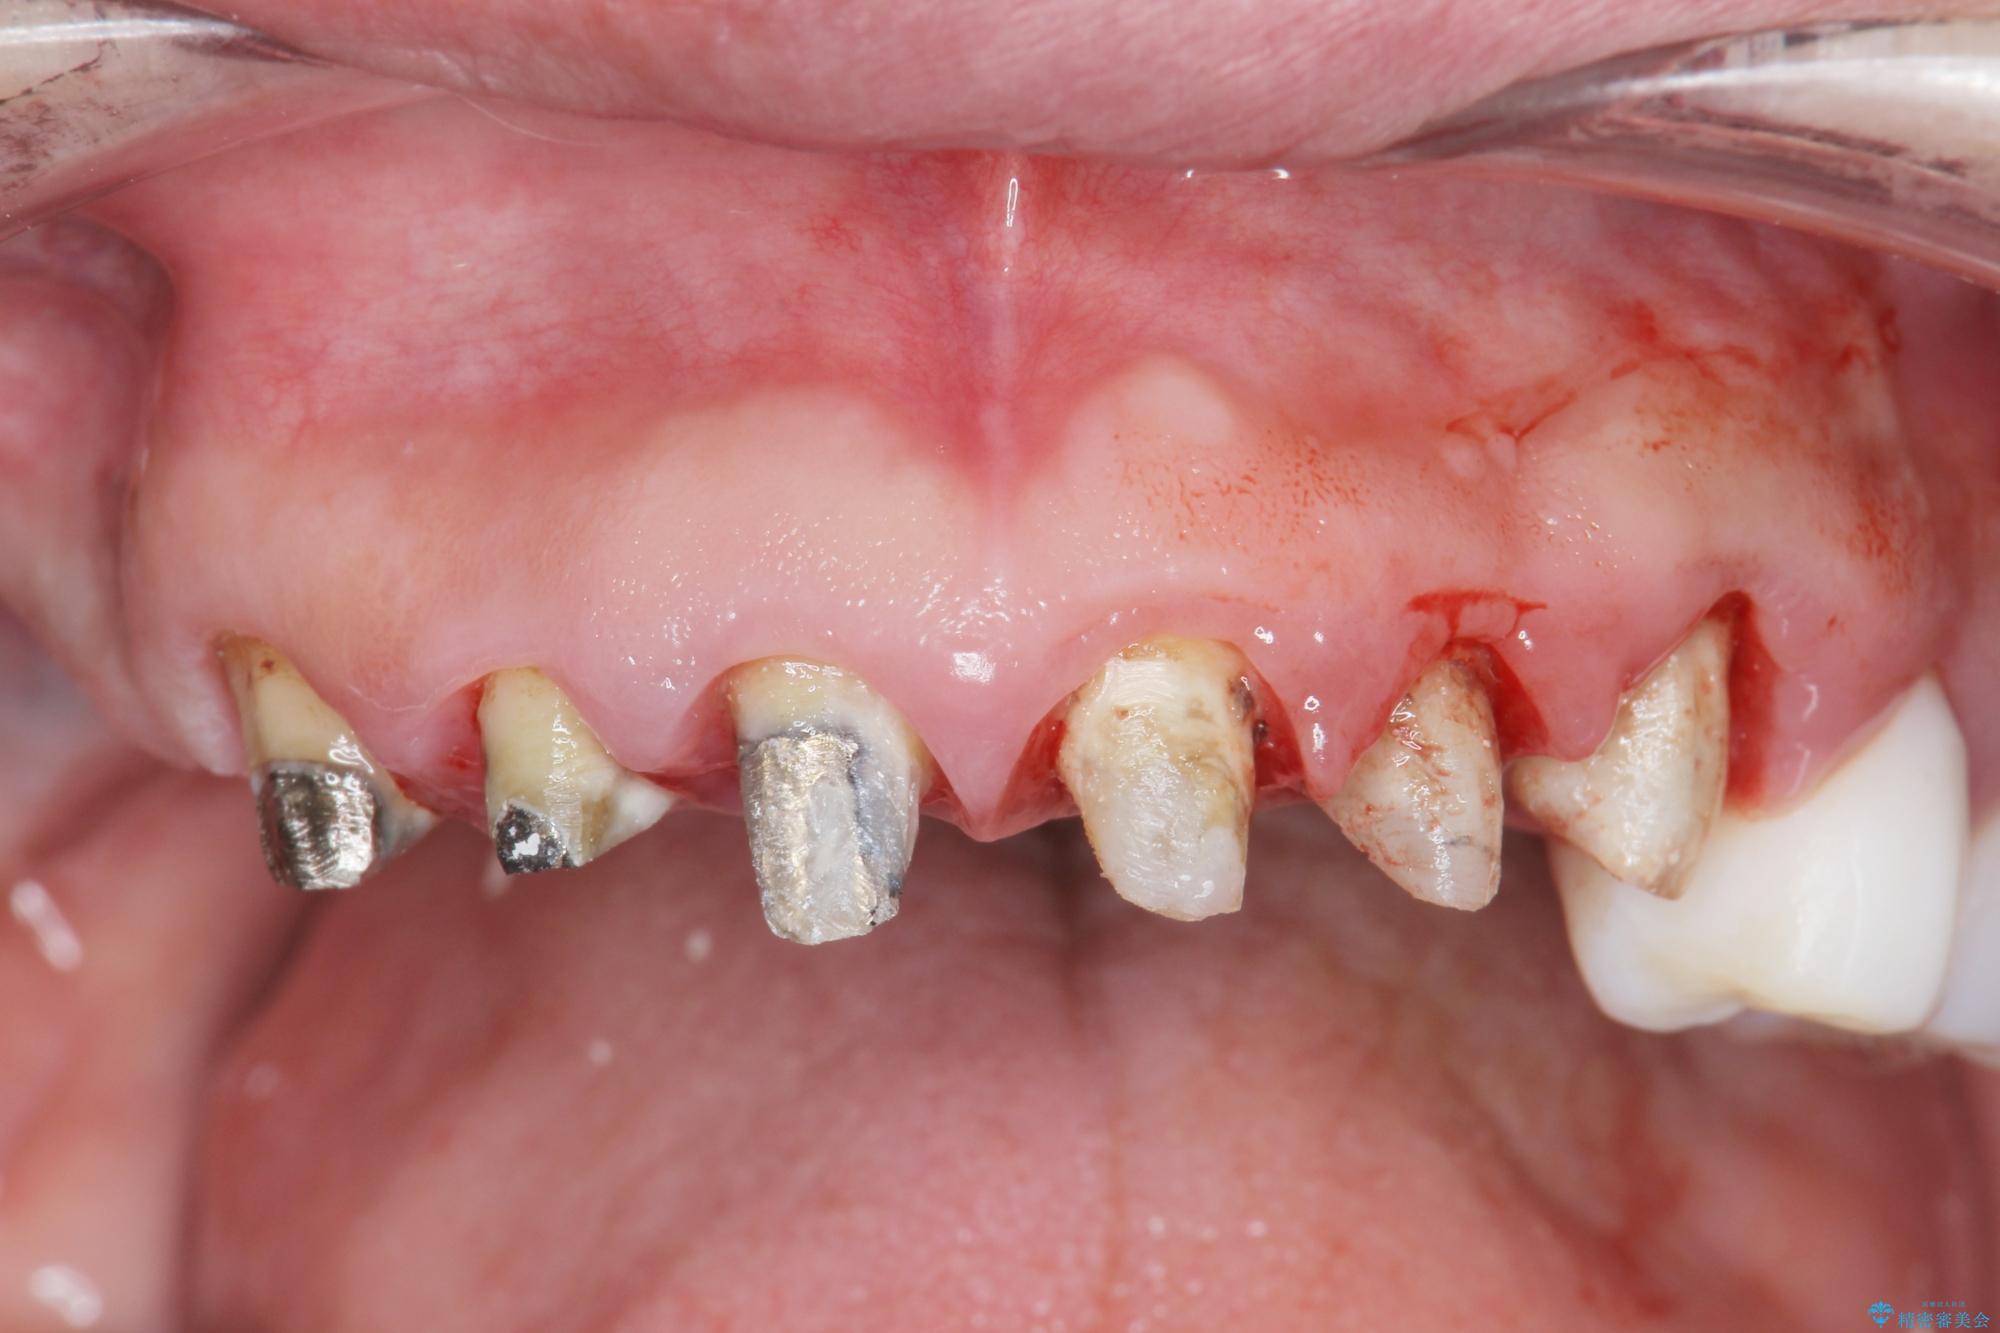

- 「セラミック治療を他院で受けたが、それ以来歯ぐきが腫れ違和感がある、改善してほしい。」と歯ぐきの状態改善を希望され来院されました。

歯周組織検査を行うと歯ぐきからは容易に出血し、X線検査より歯とセラミッククラウンの適合が悪い(ピッタリと合っていない)状態が示唆され、歯ぐきの炎症を惹起している状態でした。

セラミッククラウンを除去し仮歯を装着し、歯周外科手術を行い歯ぐきの状態を改善したのち、適合の良いセラミッククラウンを再作製をする治療計画としました。